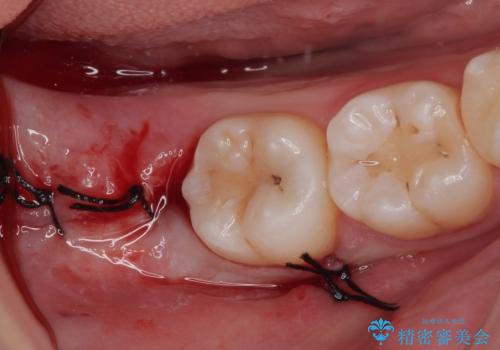

親知らずを抜きたい 親知らず抜歯

右下の親知らずを抜きたい 親知らず抜歯